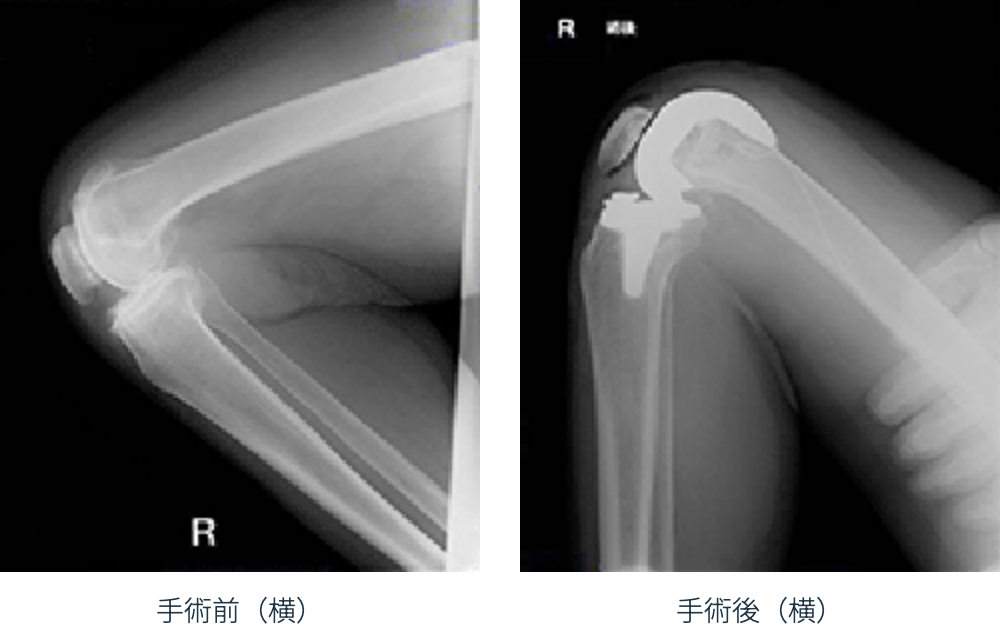

現在、変形性膝関節症の手術で最も多く行われているのが、人工膝関節置換術です。 関節全体を入れ換える手術ではなく、痛みの原因であるすり減った軟骨と傷んだ骨の表面部分を切除して、 金属やプラスチックでできた人工の関節に置き換える手術です。 痛みの大きな改善と、早期の回復が期待できる治療法です